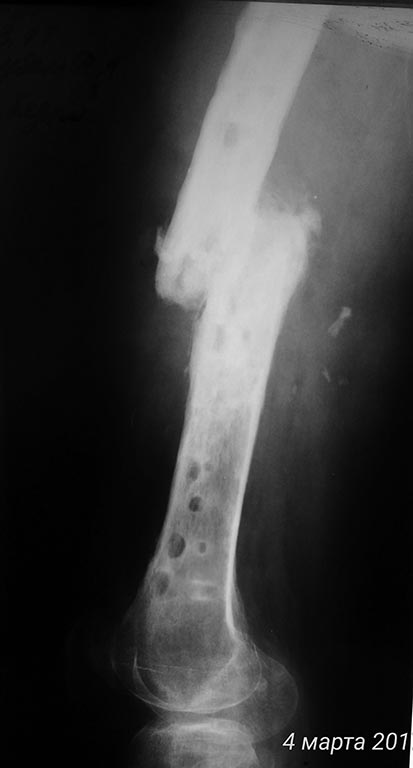

Помогите, пожалуйста, определиться с объёмом и методом оперативного вмешательства. Больной К., 1983 г.р. попал ко мне (в отделение гн.хирургии) 02.03.17. Краткий анамнез (со слов больного и согласно предоставленной мед.документации): 2013г - о/перелом ср/3 правой бедренной кости. АВФ. Затем конверсия на БИОС. В позднем послеоперационном периоде - нагноение.

Диагностирован ХТО средней трети правого бедра, свищевая форма.

2014г - удаление м/к, некрэктомия, стержневой АВФ. 2015г - рецидив. Повторная СНЭ, сегментарная резекция с\3 правой бедренной кости, пермонтаж АВФ.

Сентябрь 2016г - демонтаж АВФ. Больной ходил с полной опорой, в бандаже. В середине феврале 2017 обострение процесса, выраженный отек правого бедра, лихорадка. Пациент самостоятельно дренирует очаг.

Локально при поступлении: по латеральной пов-ти ср/3 правого бедра п/о рубцы, 2 свища с гнойно-геморрагическим отделяемым, дно - бедренная кость. На рентгенограмме: перелом не сросся. Выполнена фистулография.

Дополняю рентген архив

Прокомментирую:

самый первый снимок от 12.2016

Последние от 02.2017.

По рентгенограммам - тотальный остеомиелит бедренной кости. Для подтверждения можно сделать спиральную КТ. В Советское время выполнялись трепанации кости, долговременные активные промывные системы, эндостальное облучение кости лазером и т. п. Длительный постельный режим, огромный расход биологически активных препаратов, непрерывный врачебный уход... И это только для санации очага. Если нет возможности тотального эндопротезирования, то ампутация. И, так - делают!